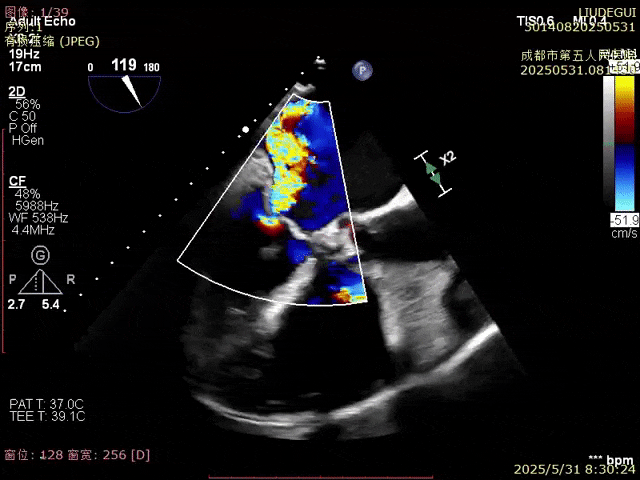

即刻反流得到明顯改善